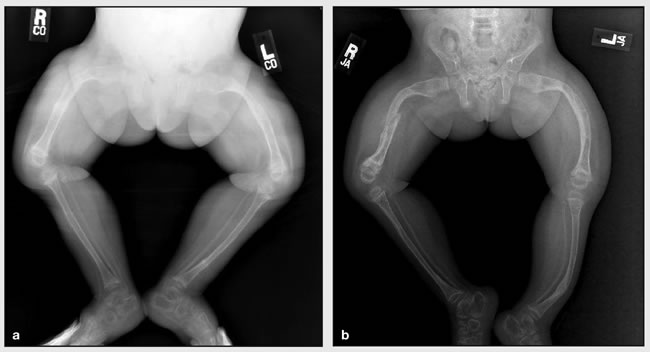

Osteogenesis imperfecta (fragilitas ossium hereditaria, Ekmanova-Lobsteinova choroba, anglicky brittle bone disease) je heterogénna skupina dedičných chorôb spôsobených rôznymi geneticky podmienenými poruchami kolagénu typu I. Dedičnosť je pri včasnej forme autozomálne recesívna, pri neskorej forme je autozomálne dominantná. Toto ochorenie je charakterizované zvýšenou krehkosťou kostí a zvýšeným výskytom zlomenín, kostné deformity, strata sluchu, lámavosť zubov. Osteogenesis imperfecta nie je úplne zriedkavé ochorenie, prevalencia je 1: 10.000-20.000.

Závažnosť postihnutia závisí na type mutácie, závažnejšie formy neprežijú intrauterinný vývoj alebo zomierajú krátko po narodení, následkom početných zlomenín. U ťažkých foriem sa môže diagnostikovať ultrasonograficky, inak je možná genetická diagnostika.